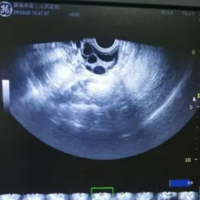

b超检查到有一个优势卵泡能证明质量是健康的吗?

问题描述:我和老公去年就商量好要一个孩子,但备孕超过半年了都一直没怀上。这个月去做B超监测卵泡,说我有一个优势卵泡,大约在约19毫米左右,还没有排出。我之前也做过,但都没有怀孕,所以我想问问有优势卵泡就能证明质量是健康的吗?最佳回答:b超检查到有一个优势卵泡不能证明质量的健康状况。女性做B超时检测到卵巢中有优势卵泡不代表一定能发育成熟,也不能说明在发育成熟后一定会排卵。有些女性如果出现卵巢功能不好...